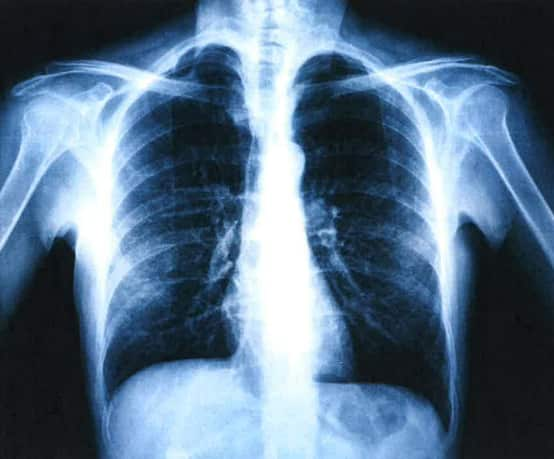

“几年前说是肺上叶被纤维化了……去年拍的片子显示肺中叶和下叶都开始有纤维化了,比以前严重。”

西悉尼大学医学教授林奇恩此前在接受SBS广东话节目的采访时表示,矽肺病是一种主要由吸入二氧化硅引起的肺部疾病。该疾病会造成患者肺部纤维化,出现呼吸急促、胸闷、胸痛、咳嗽、有痰、工作吃力等症状。

“当肺部组织被纤维化、积聚一些导致肺部无法交换气体的物质,这是无法逆转的。因为肺部的组织是不能重生的,因此病人的情况只会恶化。”

研究显示,在大多数情况下,矽肺病患者在早期阶段不会出现任何症状,确诊或需数年。